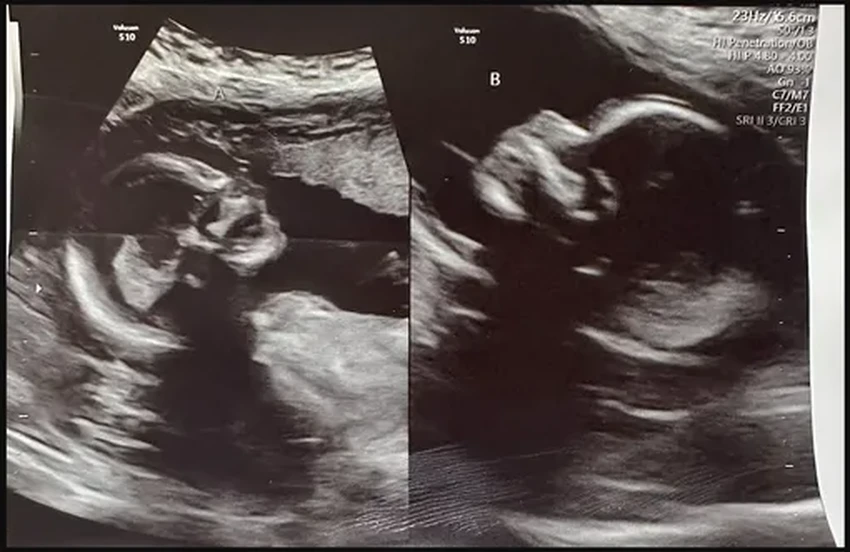

Келси жила с этой особенностью, даже не подозревая о ней, пока в 17 лет врачи не поставили диагноз. И вот теперь, будучи мамой троих прекрасных детей (7, 4 и 2 лет), она готовится к рождению еще двоих. Любопытно, что все предыдущие беременности протекали в одной матке — природа будто решила на этот раз «включить» и вторую.

Давайте разберемся. Специалисты предполагают следующую цепочку событий: «Скорее всего, в каждом яичнике созрело по яйцеклетке. Они отправились в путь — каждая в свою фаллопиеву трубу. А дальше сперматозоиды оплодотворили каждую из них уже в отдельных „апартаментах“ — правой и левой матке».

Шансы на такое событие астрономически малы — примерно 1 к 50 миллионам. Последний раз мир наблюдал подобное в 2019 году в Бангладеш, где между рождением «двойняшек» прошло целых 26 дней. Вот уж действительно, каждый ребенок решил появиться в свой особенный день.